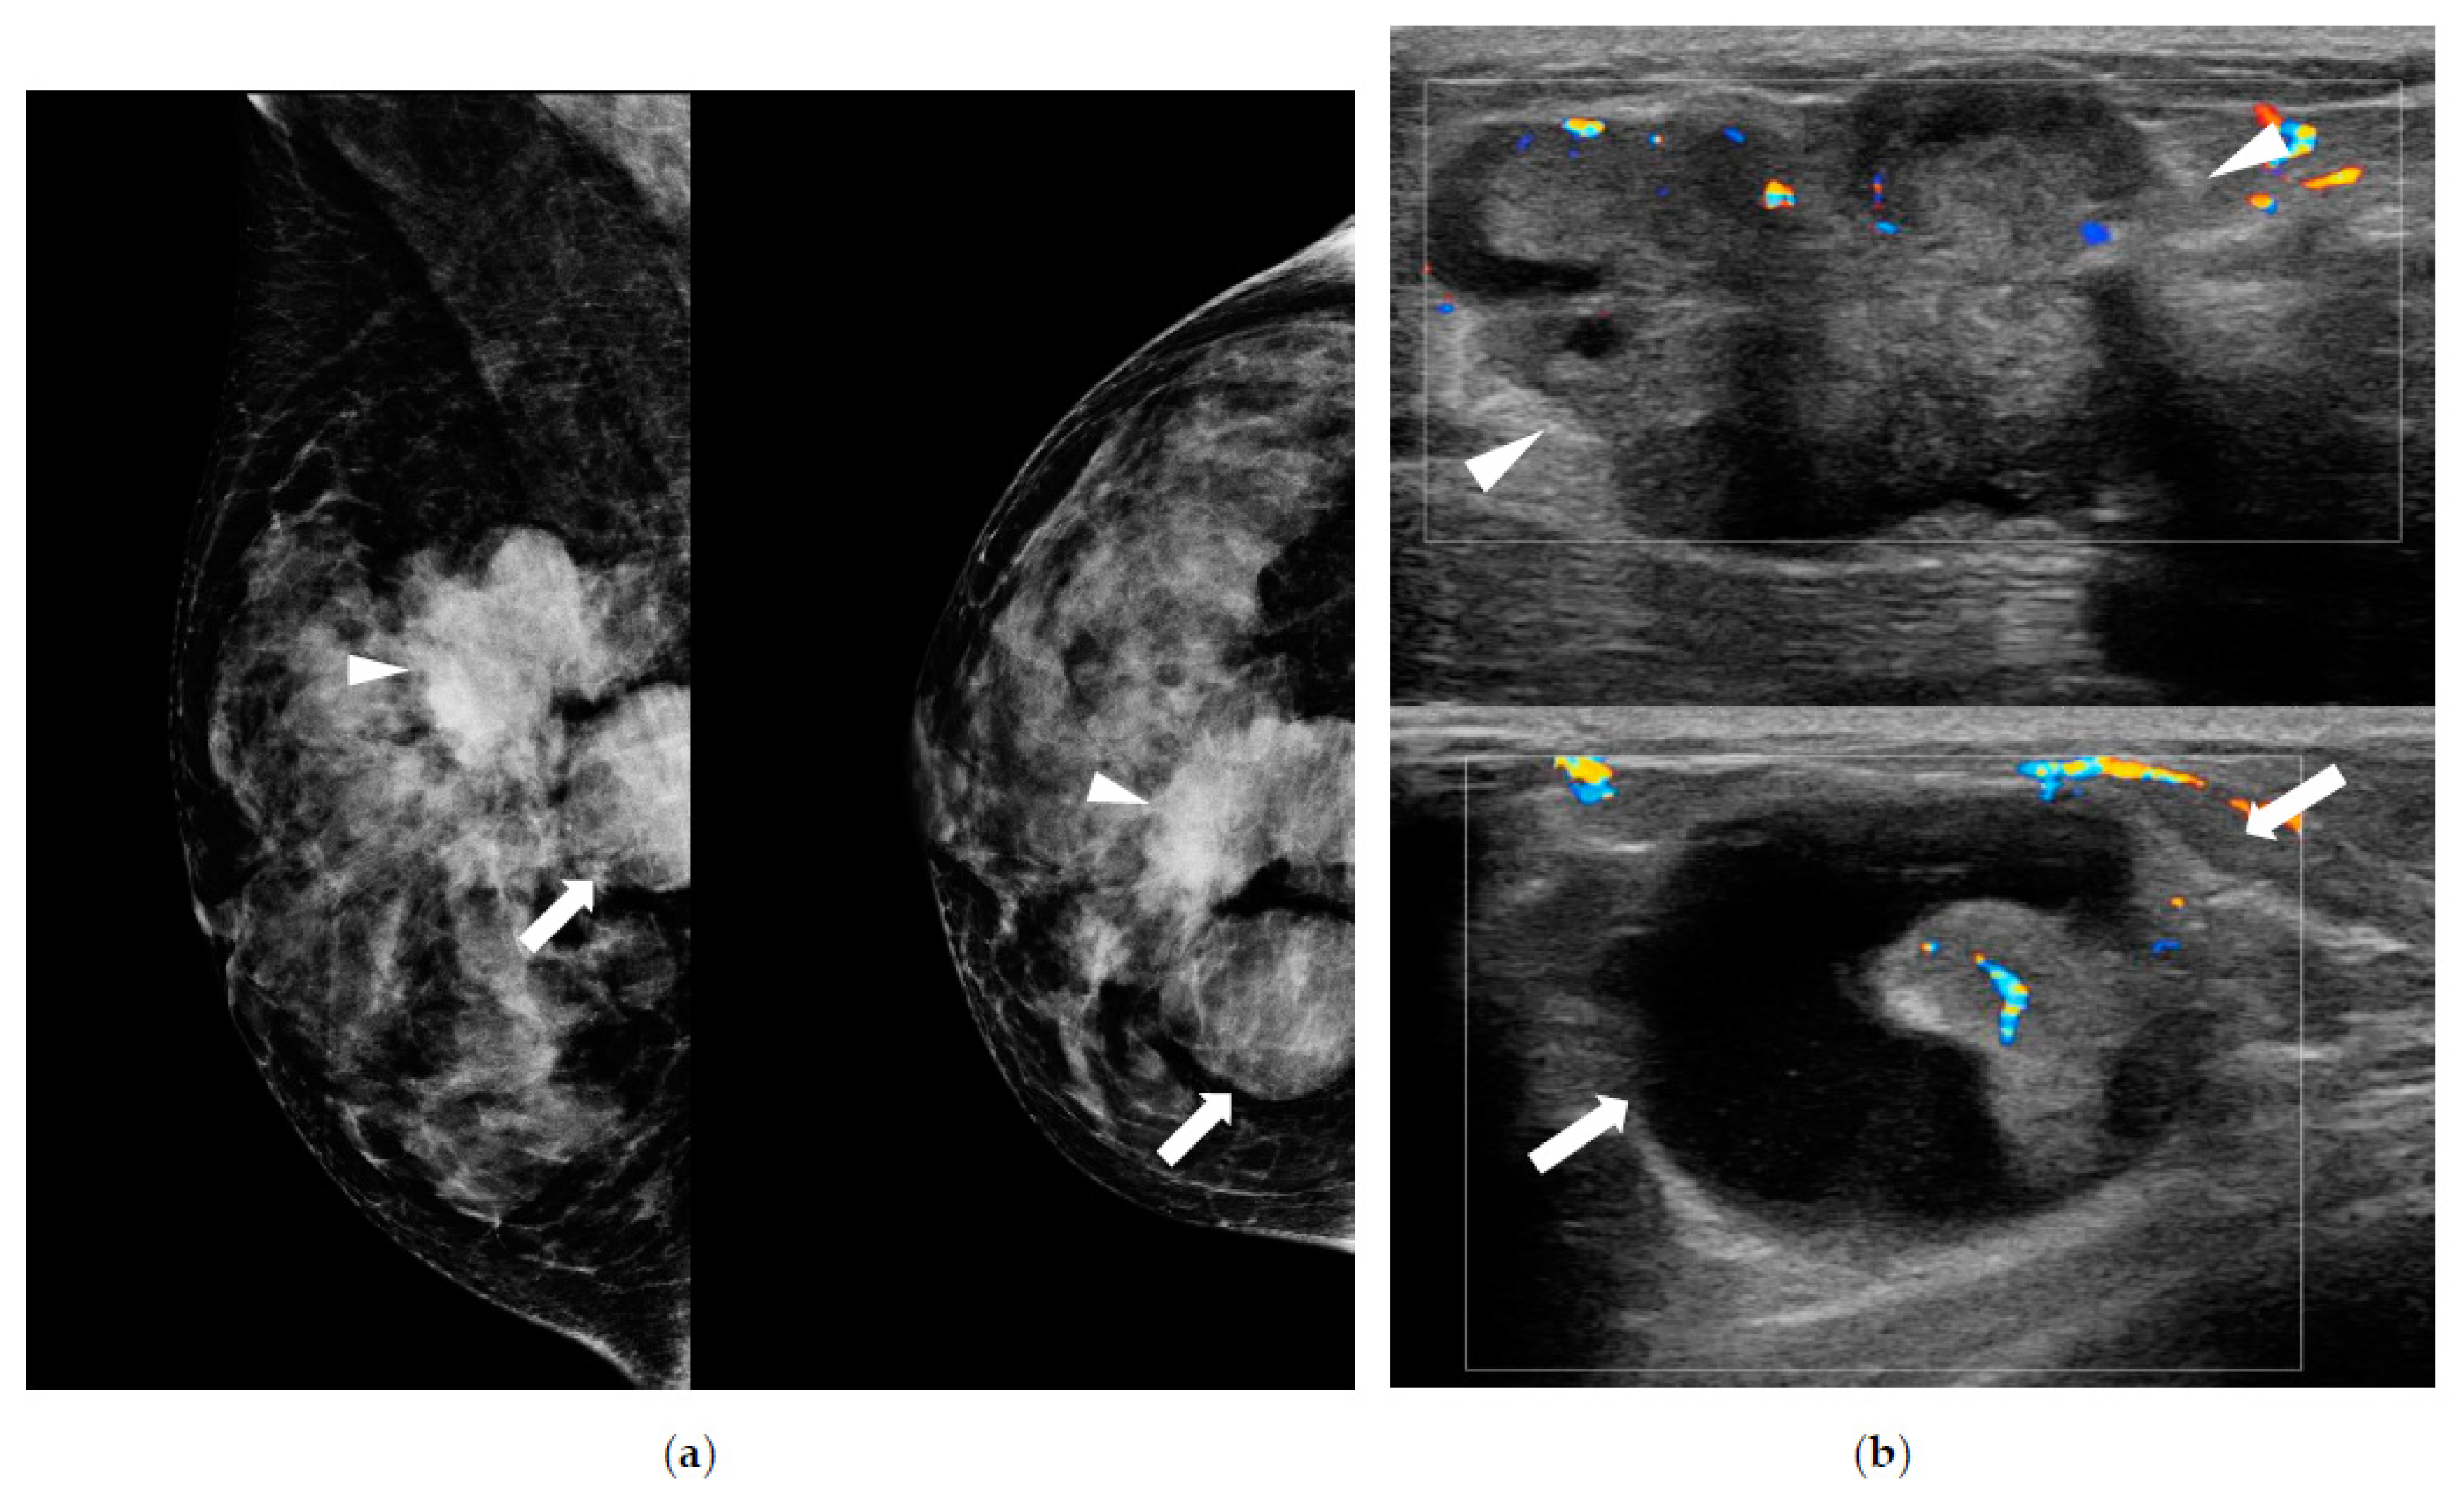

| Density on MG (n) Fatty Dense | 227 46 (15.30%) 181 (60.10%) | 136 16 (11.8%) 120 (88.2%) | 54 9 (16.7%) 45 (83.3%) | 37 21 (56.8%) 16 (43.2%) | <0.001 |

| Visibility on MG (n) (−) (+) | 227 129 (56.8%) 98 (43.2%) | 136 95 (69.9%) 41 (30.1%) | 54 29 (53.7%) 25 (46.3%) | 37 5 (13.5%) 32 (86.5%) | <0.001 |

| Type on MG Mass Asymmetrical Calcification only | 98 52 (53.0%) 38 (38.8%) 8 (8.2%) | 41 15 (36.6%) 23 (56.1%) 3 (7.3%) | 25 13 (52.0%) 8 (32.0%) 4 (16.0%) | 32 24 (75.0%) 7 (21.9%) 1 (3.1%) | 0.01 |

| BI-RADS (n) Category 3 Category 4A Category 4B Category 4C Category 5 | 301 7 (2.30%) 242 (80.4%) 31 (10.3%) 12 (4.0%) 9 (3.0%) | 192 4 (2.1%) 168 (87.5%) 18 (9.4%) 2 (1.0%) 0 (0%) | 68 3 (4.4%) 54 (79.4%) 7 (10.3%) 2 (2.9%) 2 (2.9%) | 41 0 (0%) 20 (48.8%) 6 (14.6%) 8 (19.5%) 7 (17.1%) | <0.001 |

| Shape on US (n) Oval to round Irregular | 295 196 (65.10%) 99 (32.90%) | 190 133 (70.0%) 57 (30.0%) | 64 44 (68.8%) 20 (31.3%) | 41 19 (46.3%) 22 (53.7%) | 0.003 |

| Posterior feature on US (n) Enhancement Shadowing No | 295 71 (23.60%) 4 (1.30%) 220 (73.10%) | 190 38 (20.0%) 2 (1.1%) 150 (78.9%) | 64 13 (20.3%) 1 (1.6%) 50 (78.1%) | 41 20 (48.8%) 1 (2.4%) 20 (48.8%) | <0.001 |